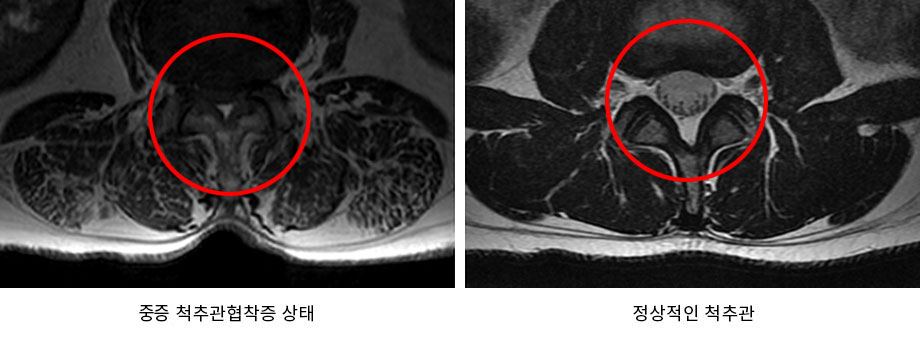

나이가 들면 우리의 몸도 같이 나이가 들게 됩니다. 우리 몸을 지탱해주는 척추 또한 나이를 먹으면서 퇴행되어 기능이 떨어지고, 약해지게 됩니다. 이러한 퇴행으로 인해 발생하는 대표적인 척추질환이 척추협착증입니다. 척추협착증은 척추를 둘러싸고 있는 근육과 인대가 퇴행되어 제 기능을 하지 못하게 되면서 척추관 내 황색인대가 비정상적으로 부풀어 오르게 됩니다. 척추관 내 황색인대가 부풀어 오름에 따라 척추관의 공간이 줄어들게 되면서 신경을 압박하게 되는데, 그로 인해 통증이 발생하는 질환입니다.

척추관 내 황색인대가 부풀어 오르는 이유는 우리 몸을 지탱하기 위해서입니다. 퇴행이 진행되면 척추를 비롯하여 척추 주변의 근육과 인대, 디스크 등도 퇴행이 되면서 기능이 떨어지고, 약해지게 됩니다. 척추를 지탱하는 근육과 인대, 디스크 등의 구조물들이 약해지게 되면 우리 몸은 어떻게든지 이를 지탱하기 위해 노력을 하게 되는데, 이 과정에서 황색인대의 몸집이 굵어지고, 단단해지면서 척추관을 좁아지게 만듭니다.

간혹, 통증의 차이가 있는 것을 어떤 날은 좁아진 척추관이 넓어졌다가 어떤 날은 다시 좁아지는 것은 아닐까 하는 의문을 가질 수 있습니다. 하지만 아닙니다. 좁아진 척추관은 시간이 지난다고 해서 넓어지지 않을뿐더러 더 좋아지지도 않습니다. 또한 퇴행되어 부풀어 오른 황색인대도 원래의 크기로 되돌아가지 않습니다. 즉, 좁아진 척추관을 넓히지 않음에도 증상 개선이 가능한 이유는 척추를 지탱하는 근육과 인대에 있습니다.